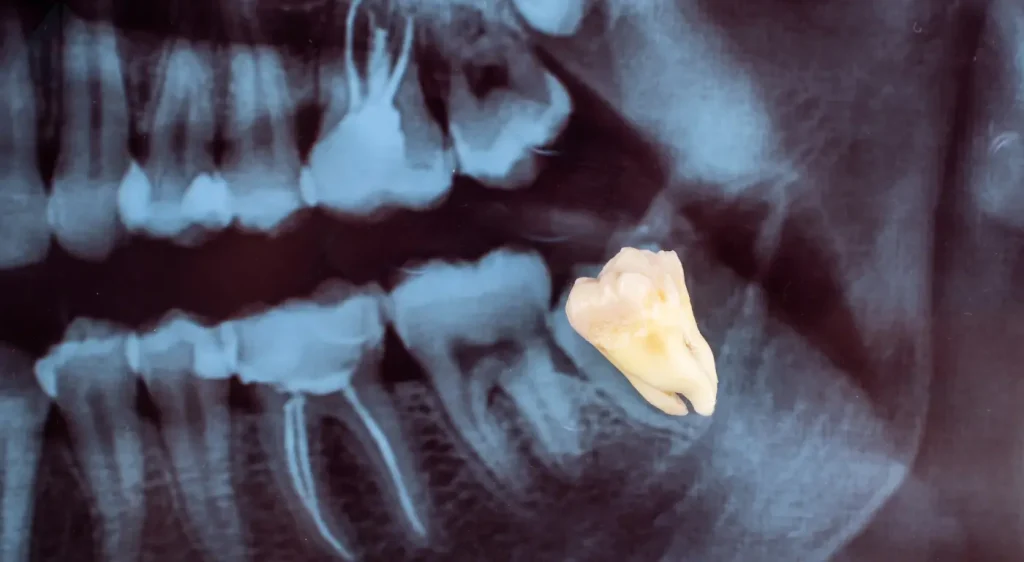

Potential Risks: It’s true that the potential for complications is higher in adults, as the graphic above clearly illustrates. A slower healing process and a slightly higher risk of nerve irritation are all factors we consider.

However, it is crucial to understand that these risks are dramatically minimized with an experienced surgeon and advanced technology. For example, Dr. Carranza’s use of 3D CBCT scanning allows for a precise surgical plan that navigates around critical structures, thereby protecting your health and ensuring a predictable outcome.